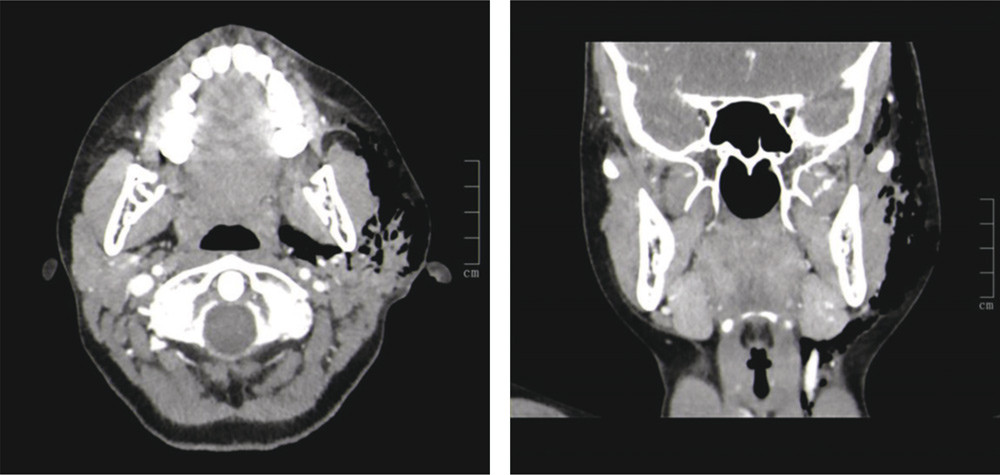

CT-undersøkelse med intravenøs kontrast ble gjort siden man mistenkte raskt utviklende nekrotiserende fasciitt på grunn av ultralydfunnet. Den viste uttalt emfysem i hele venstre ansiktshalvdel, men ingen tegn til inflammasjon eller abscessdanning (bildene – aksialt og koronalt plan, luften ses i sort). Pasienten hadde økende smerte, hevelse og rødme neste døgn og ble undersøkt i narkose med punksjon, aspirasjon og sondering av ductus parotideus, uten funn av noe patologisk utover luft. Denne lot seg lett aspirere, og da gikk hevelsen tilbake. Jenta ble neste dag spontant bedre og antibiotikabehandlingen seponert. Tilstanden ble betraktet som pneumoparotitt. Hun har i etterkant hatt flere residiv, som er blitt spontant bedre.